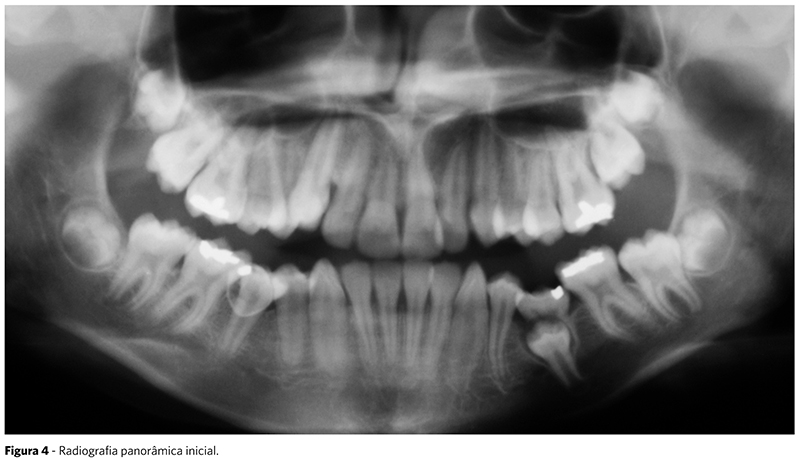

Na radiografia panorâmica inicial, observou-se a presença de todos os dentes permanentes, incluindo a cripta dos terceiros molares, além dos dentes 75 e 85 em processo final de risólize (Fig. 4).